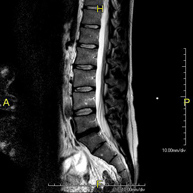

- Lumbar spine MRI

This non-invasive diagnostic procedure uses an electromagnetic field and radio waves (from a transmitter and receiver) to acquire high-definition anatomical images of the lumbar and sacral regions. It is a radiation-free procedure. Indicated for: trauma, sciatica, herniated discs, tumours, infections.